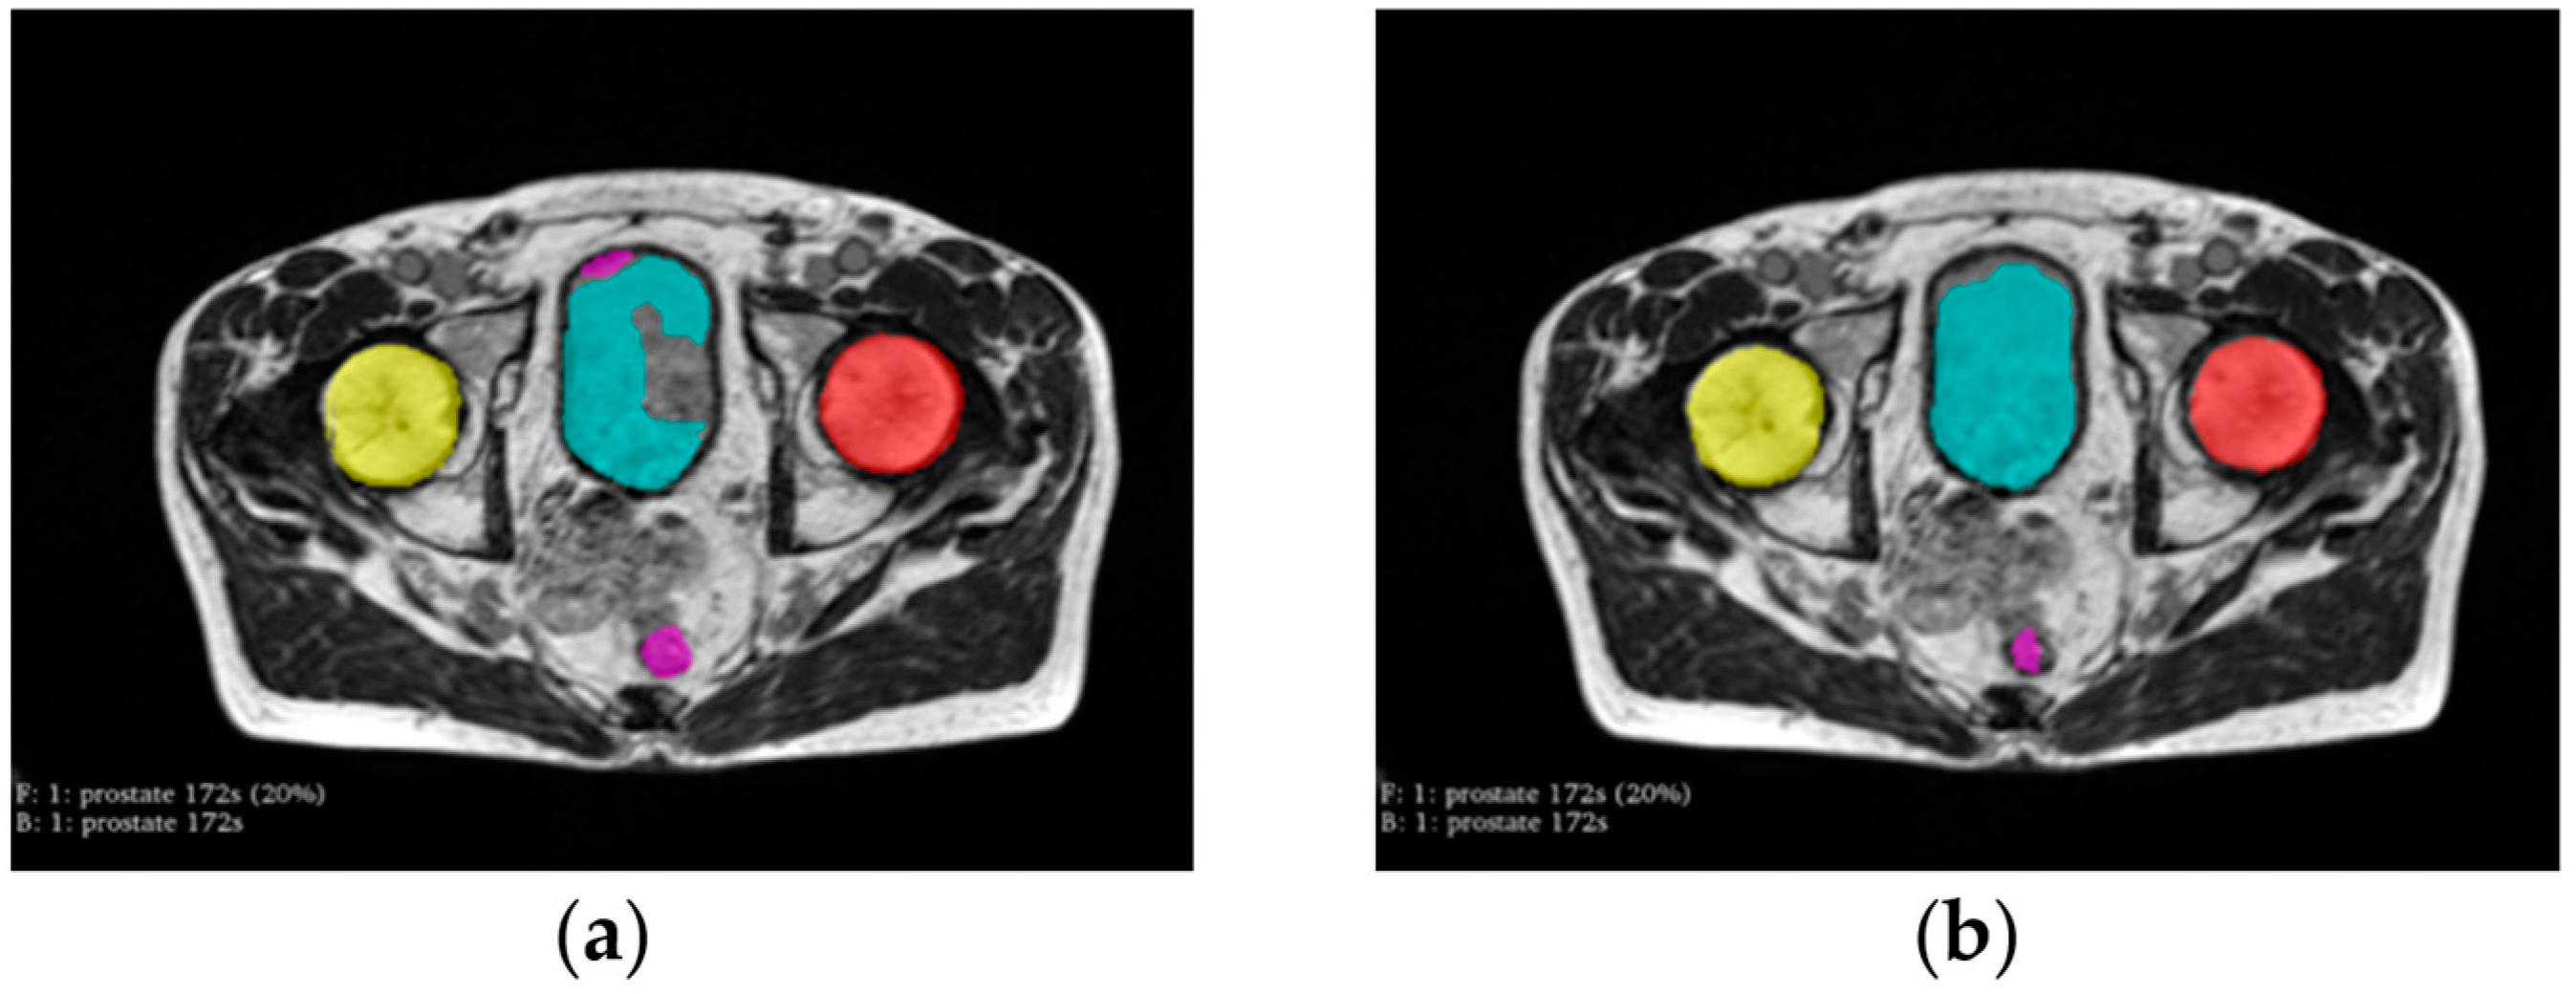

2.2. Preprocessing

2.4. Post-Processing